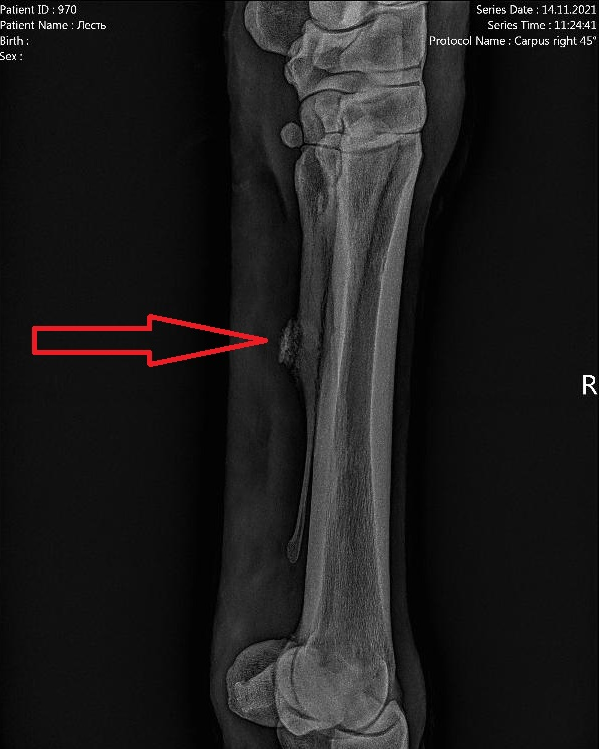

Сделали рентген и виновником наших бед оказался растущий накостник, на одном из старых переломов грифельной косточки. Возможно, Леся как-то его задела, ударила или еще как-то травмировала.

Рентген. Накостник слева на снимке по стрелке.

Такие накостники, обычно удаляют. Делают операцию, но учитывая Лесин возраст, было принято решения убрать его медикаментозно. Есть специальные блистеры, их нужно втирать каждый день в область накостника и есть шанс, что накостник или исчезнет или по крайней мере, станет меньше. Накостники, особенно такой неровной формы неприятны тем, что могут задевать сухожилие или связки, вызывая хромоту, что и произошло в нашем случае.